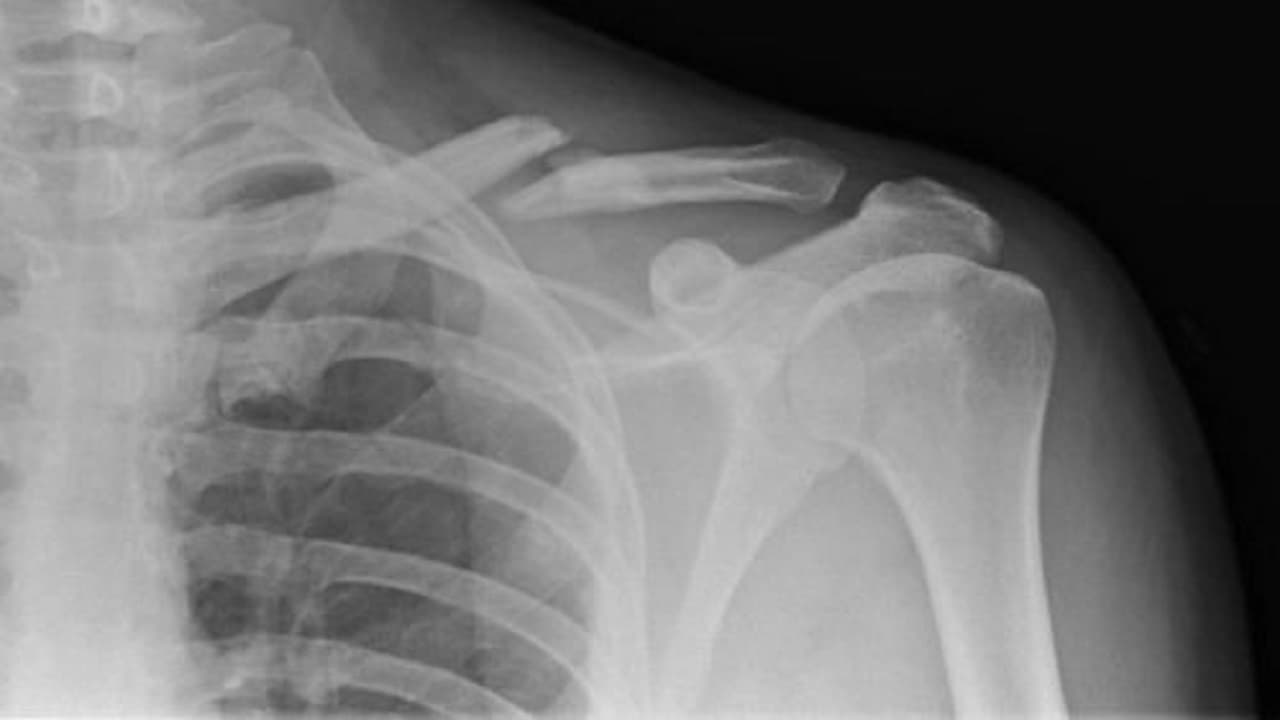

Xương đòn là chiếc xương dài nằm ngang nối giữa xương ức và vai, chịu trách nhiệm ổn định vận động của cánh tay và vai. Khi bị gãy, người bệnh sẽ có biểu hiện đau nhức dữ dội, sưng tấy, và hạn chế vận động. Ngoài việc điều trị y tế, tư thế nằm ngủ đúng đắn giúp giảm áp lực lên vùng tổn thương, giảm đau, tăng lưu thông máu, từ đó thúc đẩy quá trình liền xương nhanh hơn và nâng cao chất lượng giấc ngủ.